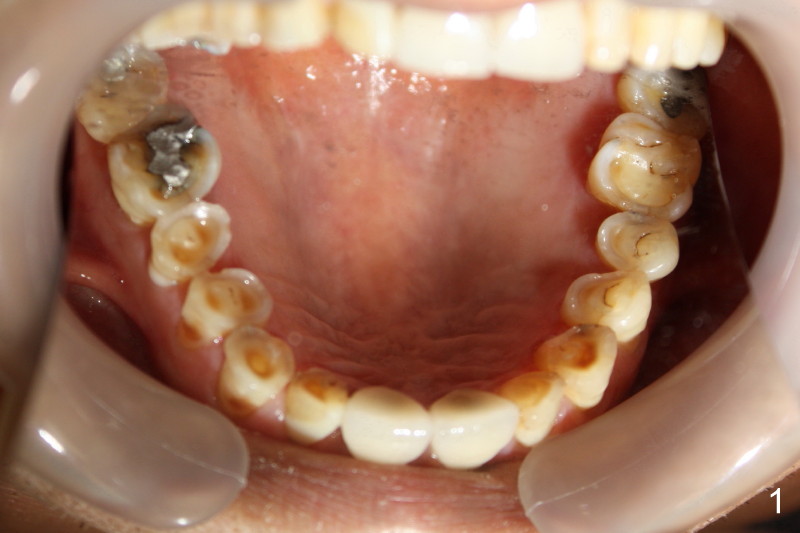

Sixty-five year old man is a bruxer, as shown in Fig.1, 2 (upper. lower arch, respectively, mirror view).  He has a night guard.  Fig.1-3 and Fig.4,5 are taken before and after crown fracture of the tooth #9, respectively.  It appears that the tooth is nonsalvageable.

Although gutta percha of #9 is overfilled, there is no active infection (Fig.3,4).  Can we place an implant immediately after extraction without loading or minimal loading?